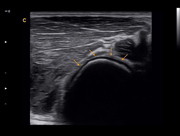

Musculoskeletal,B Mode

Subscapularis Tendon, B Mode